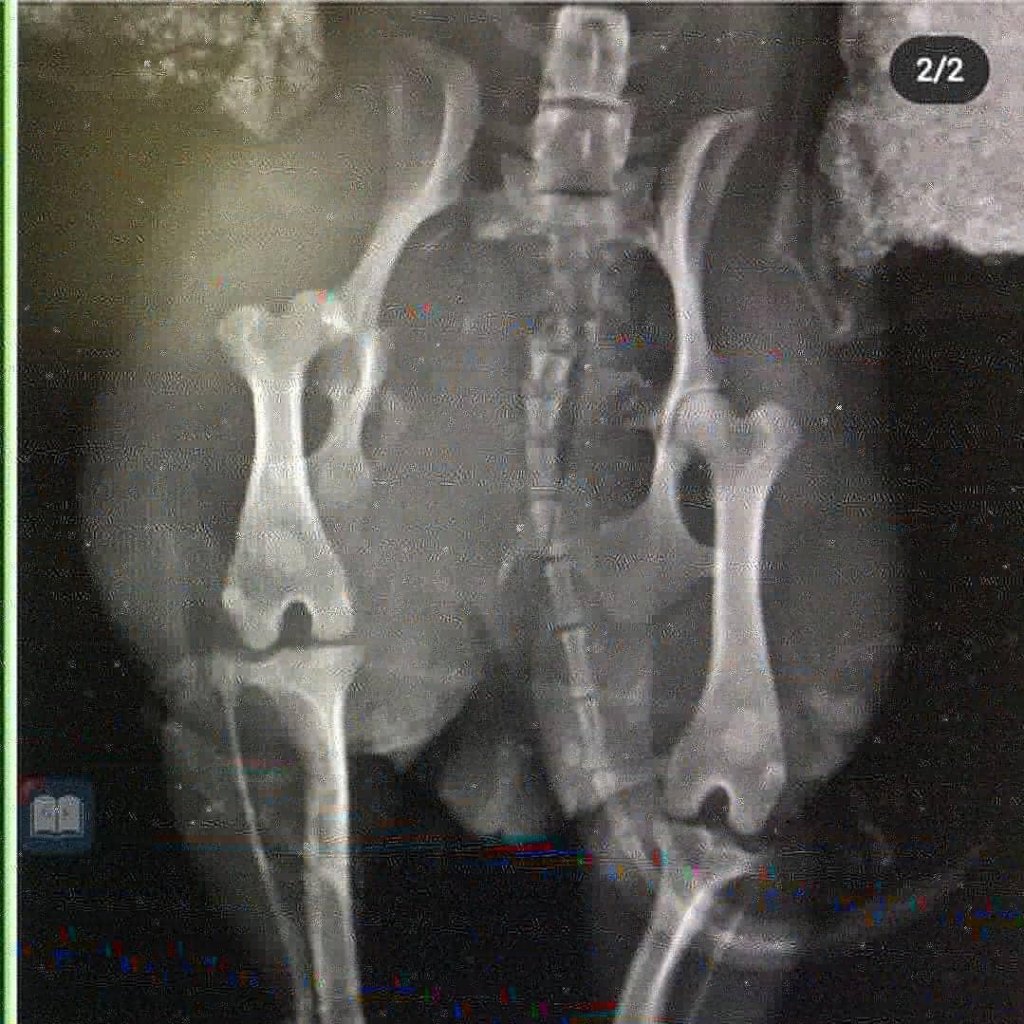

Photo 2: We named her Marla, a senior dog who was suffering from a large aggressive tumor. We were able to remove it and relieve Marla of that suffering and she's in a lovely home! Look how happy she is now!